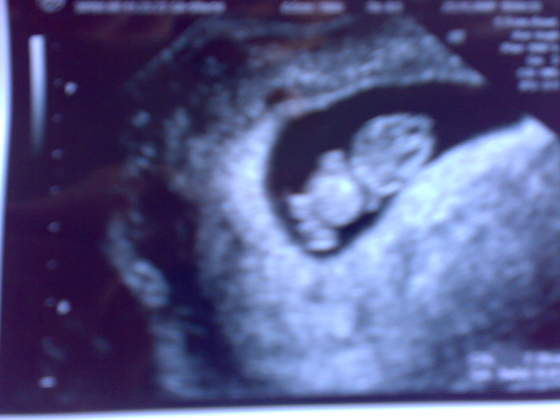

Zobacz załącznik 183765

Jestem taka szczęśliwa! To moje pierwsze USG! Według USG to już 10 tydzień, dzidzia ma prawie 3cm, machała mamusi do ekranu, cudowne uczucie!

Ps. Zdjęcie robione komórką, więc niezbyt dokładne...![]()